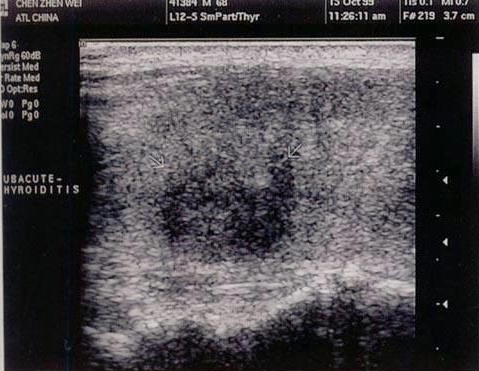

A.胆囊颈部结石并化脓性胆囊炎

C.畸胎瘤